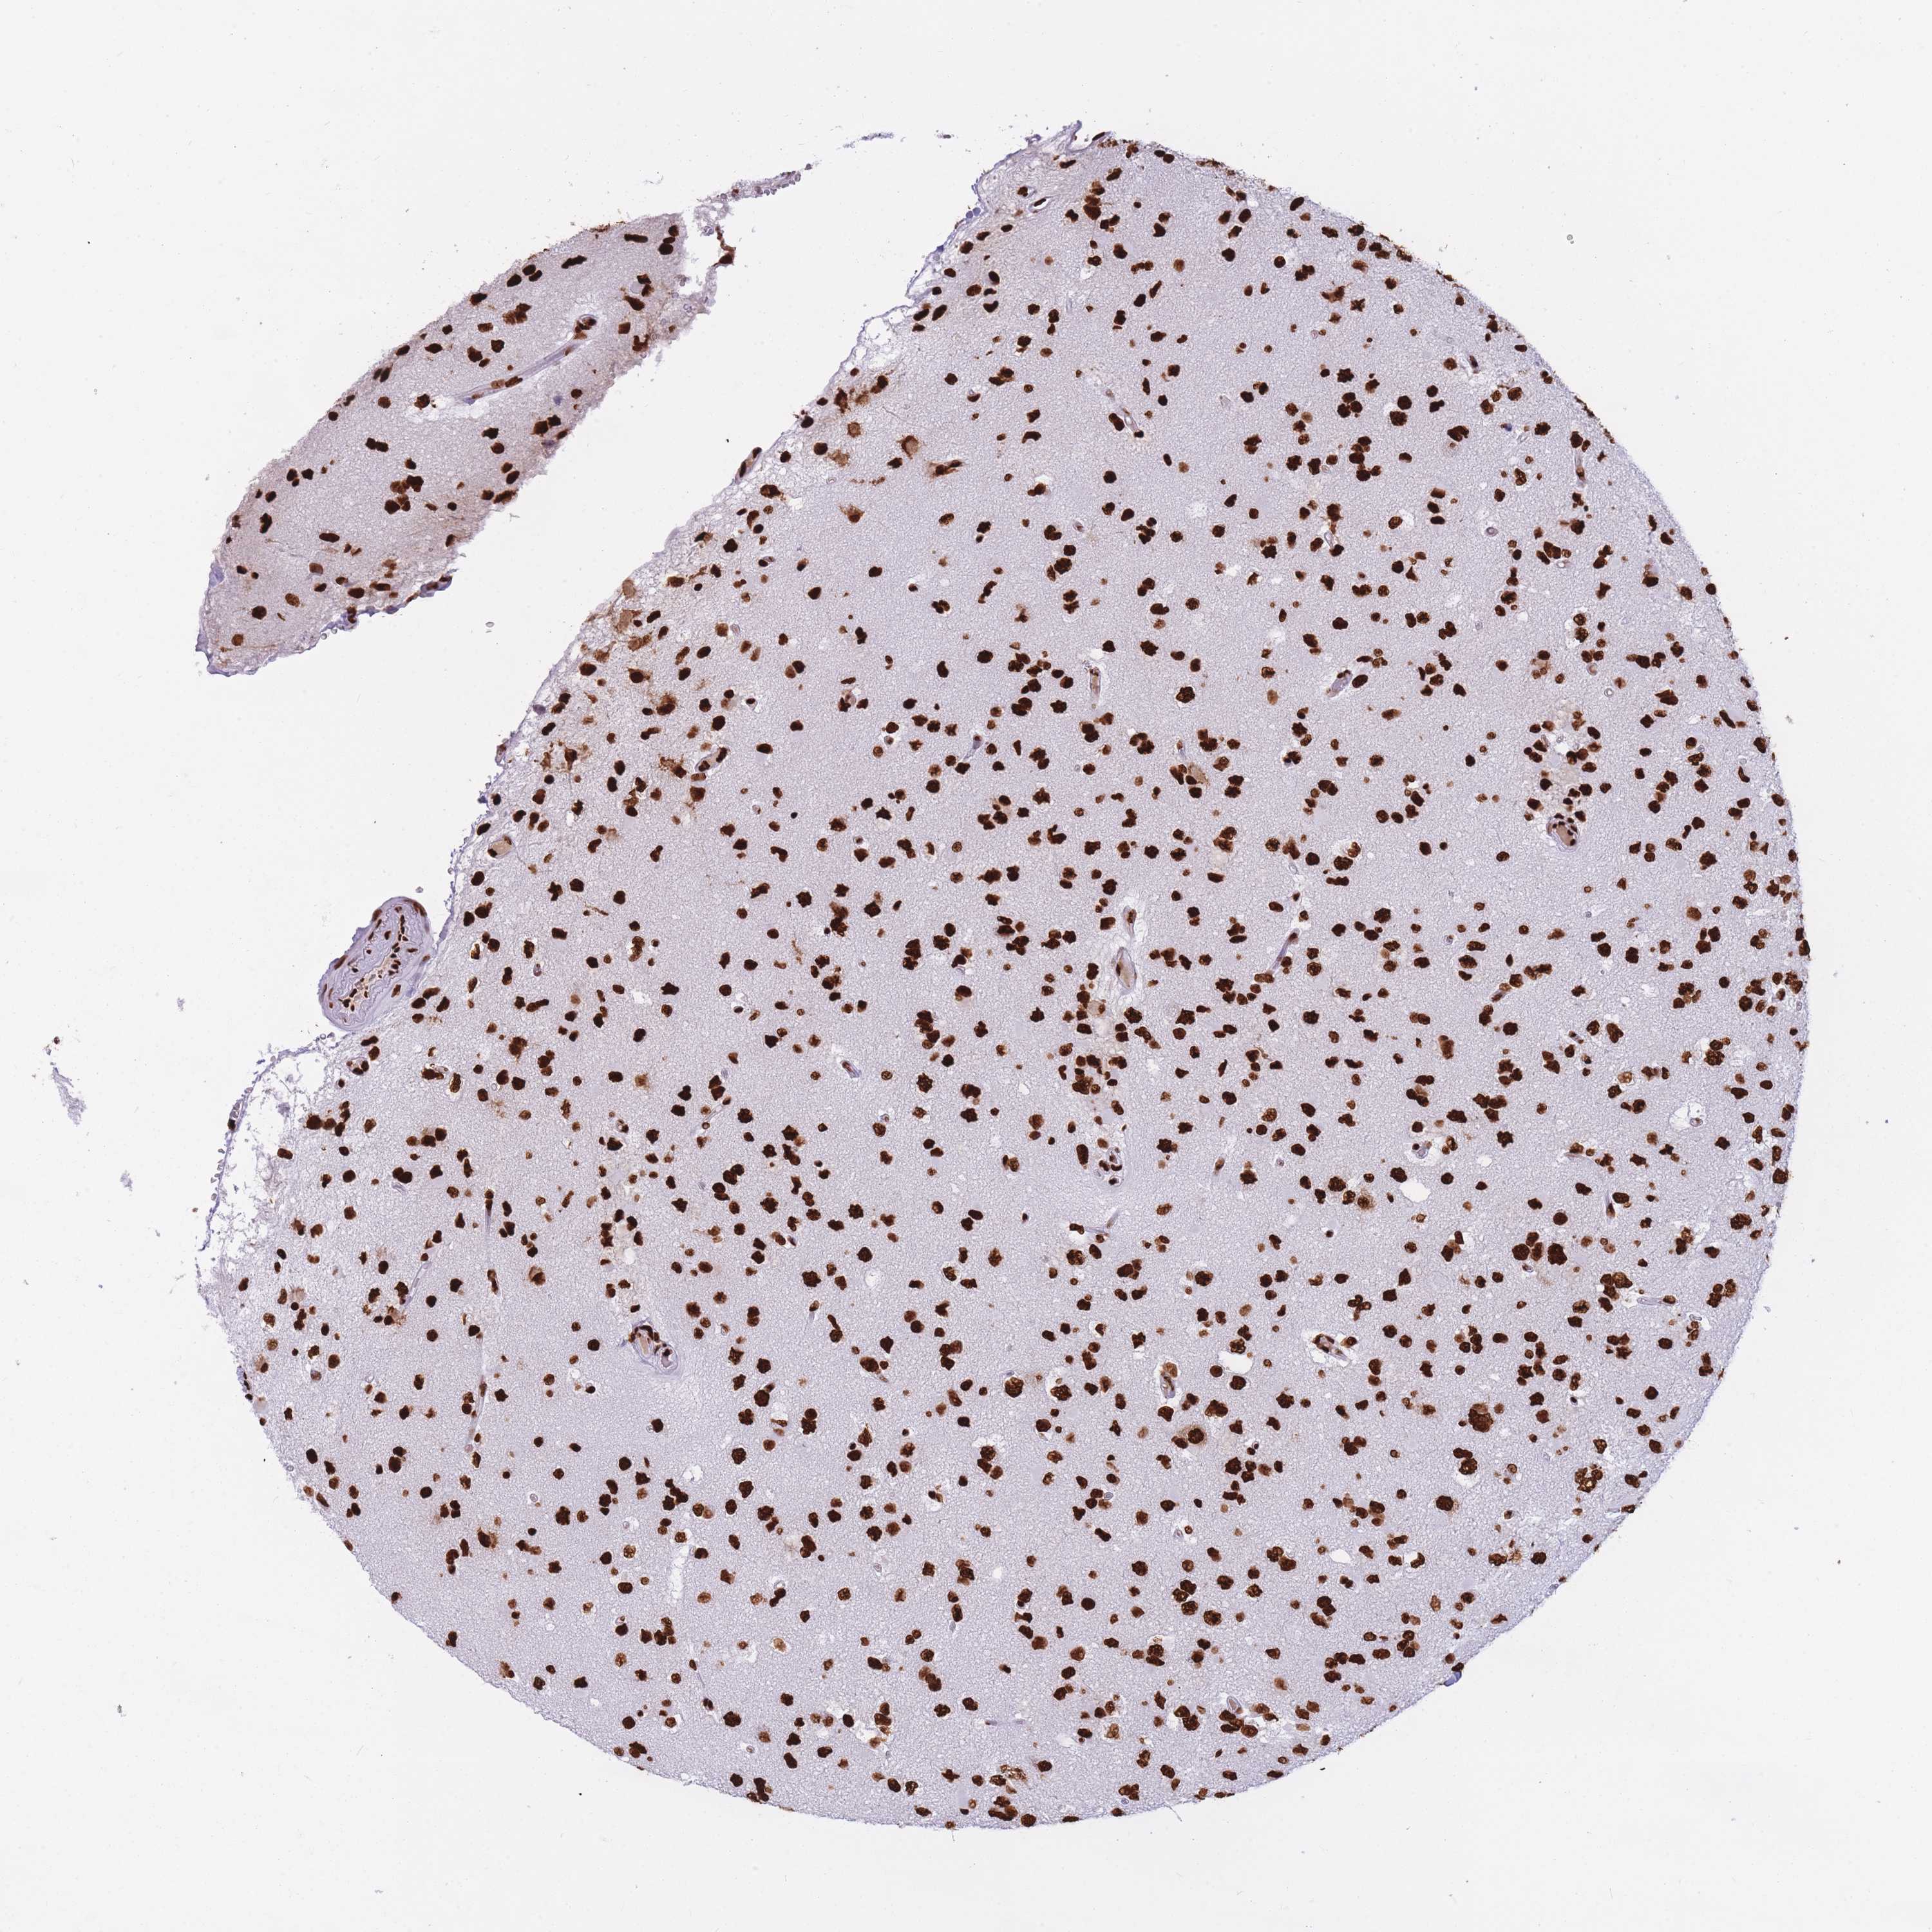

GLIOMA - Protein expressioni

A mouse-over function shows sample information and annotation data. Click on an image to view it in a full screen mode. Samples can be filtered based on level of antibody staining by selecting one or several of the following categories: high, medium, low and not detected. The assay and annotation is described here.

Note that samples used for immunohistochemistry by the Human Protein Atlas do not correspond to samples in the TCGA dataset.

Antibody stainingi

Antibody staining in the annotated cell types in the current human tissue is reported as not detected, low, medium, or high, based on conventional immunohistochemistry profiling in selected tissues. This score is based on the combination of the staining intensity and fraction of stained cells.

Each image is clickable and will lead to virtual microscopy that enables deeper exploration of all samples and also displays staining intensity scores, fraction scores and subcellular localization as well as patient and tissue information for each sample.

Antibody HPA046290

Antibody HPA049475

Antibody CAB046477

Staining

High

Medium

Low

Not detected

Intensity

Strong

Moderate

Weak

Negative

Quantity

>75%

75%-25%

<25%

None

Location

Nuclear

Cytoplasmic/membranous

Cytoplasmic/membranous,nuclear

Glioma, malignant, High grade

Glioma, malignant, Low grade